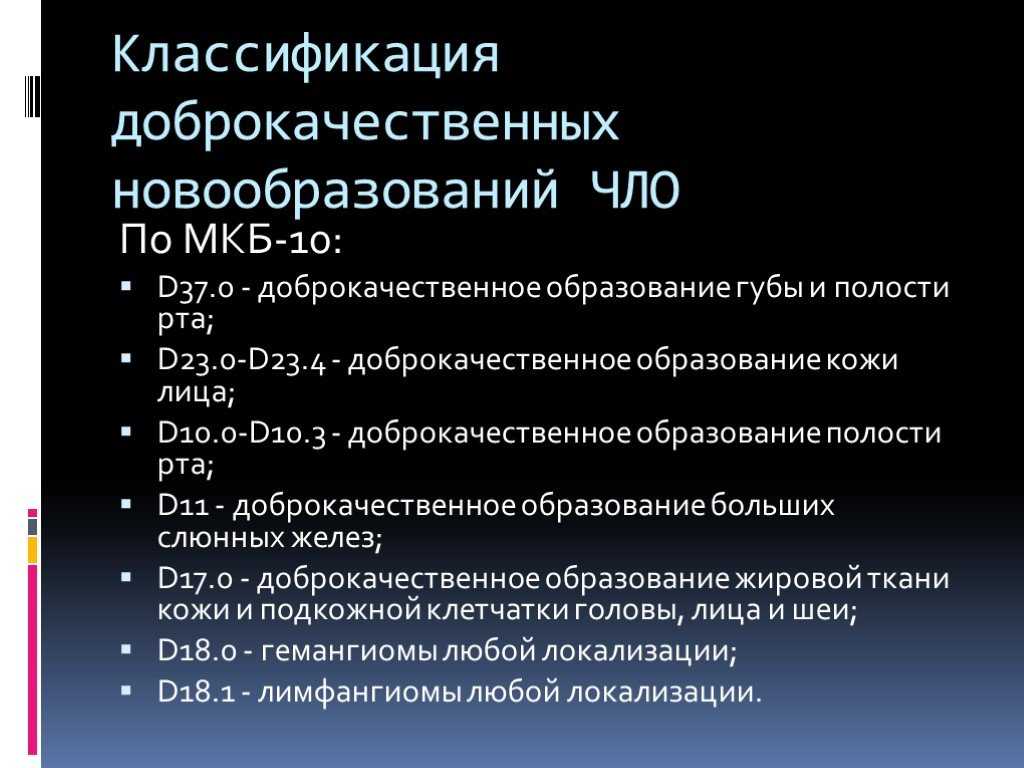

Код мкб 10 атерома головы

Код мкб 10 атерома головы 109 фото